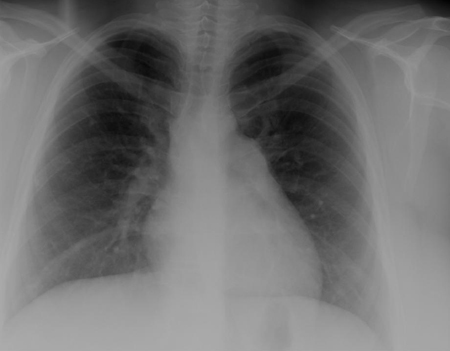

RT que demuestra una circulación pulmonar excesiva